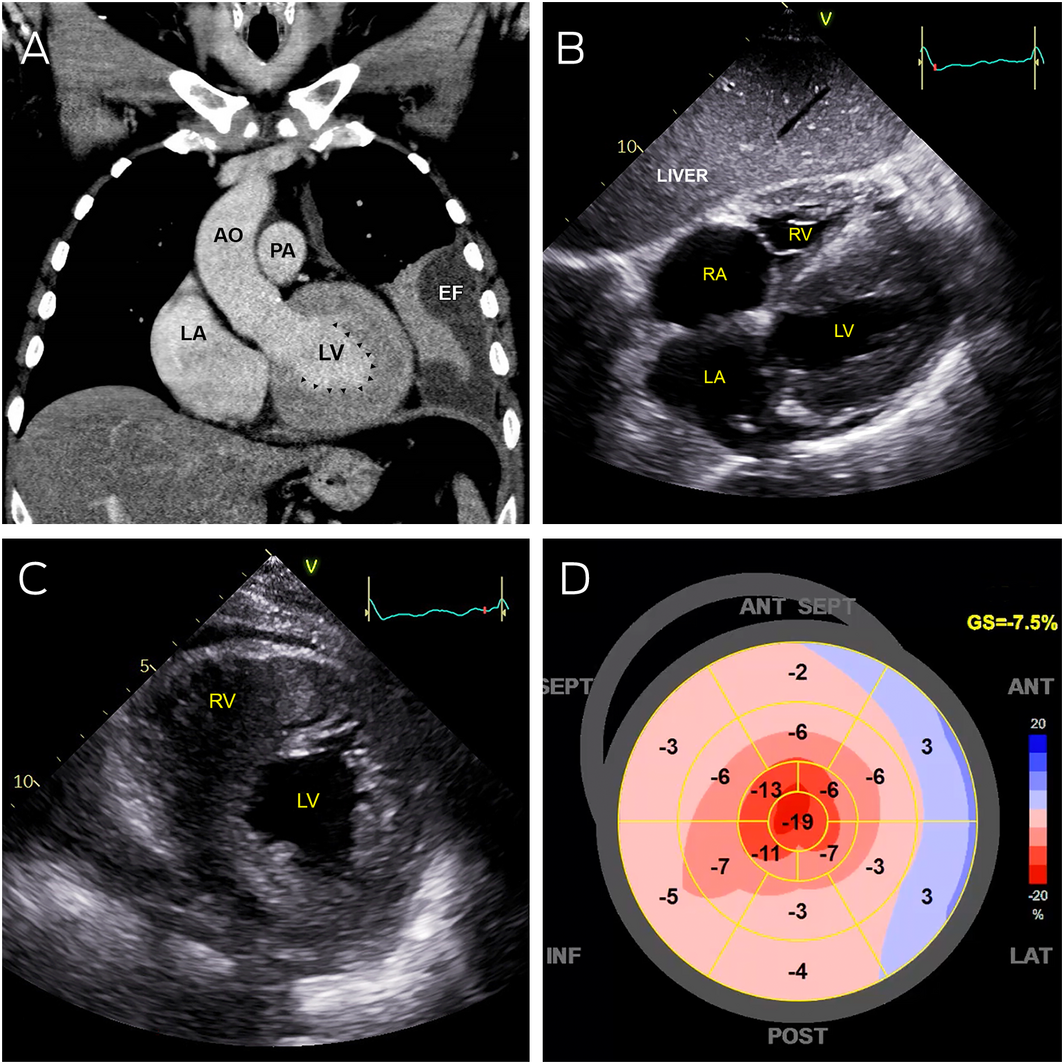

On admission, he had signs of proximal myopathy and pitting oedema to the thighs, along with non‐tender, non‐pulsatile hepatomegaly and a left lower lobe pneumonia on chest x‐ray. An electrocardiogram showed sinus rhythm, right axis deviation, right bundle branch block, and inferior Q waves. His cardiac troponin I level was elevated at 139 ng/L (RI, < 20 ng/L). He proceeded to have a chest computed tomography (CT) scan and a transthoracic echocardiogram. While showing a parapneumonic collection, the CT scan identified a markedly abnormal left ventricle, which on transthoracic echocardiography appeared as markedly increased left and right ventricular wall thickness with reduced contraction in all regions except the apex, along with severely reduced early diastolic mitral annular velocities and bi‐atrial enlargement (Box 1).

Box 1 – Abnormal cardiac imaging

AO = aorta; EF = pleural effusion; LA = left atrium; LV = left ventricle; PA = pulmonary artery; RA = right atrium; RV = right ventricle.

A: Coronal computed tomography showing severe left ventricular thickening without dilatation (arrowheads). B: Transthoracic echocardiography (subcostal view) showing severely thickened left and right ventricular walls, with severe bi‐atrial dilation. C: Transthoracic echocardiography (parasternal short axis view) showing severe increased left and right ventricular wall thickness. D: Strain map of the left ventricle showing systolic shortening of different walls of the left ventricle in a 2‐dimensional flattened image. Areas of bright red represent normal contraction while pink and blue areas represent hypocontractility. This strain map demonstrates apical preservation of contraction referred to as the cherry‐on‐top sign.